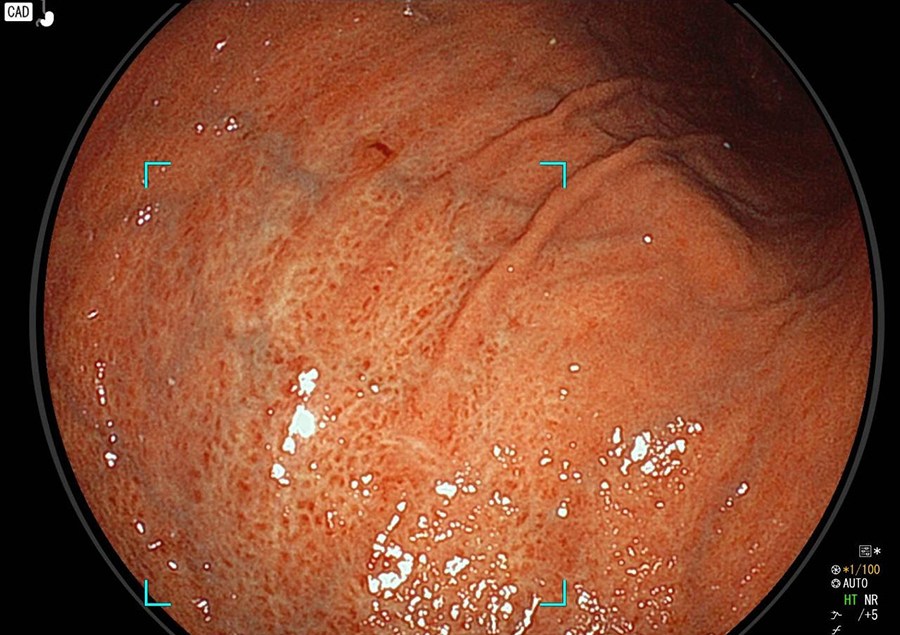

点状発赤

ピロリ菌が胃粘膜に炎症を起こし戦争状態となるため、胃粘膜が点状に赤くなります。